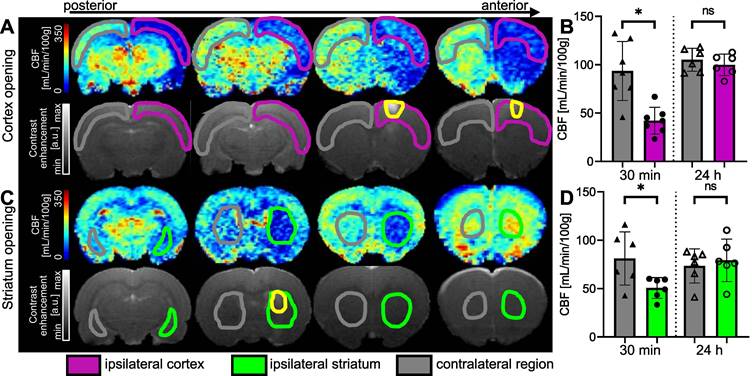

To determine the effect of FUS combined with MBs on CBF, pCASL datasets were acquired 30 min after delivering the treatment. FUS targeted the striatum in one group and the cortex in the other, with precise targeting achieved through MRI guidance.

When the right cortex was targeted (Figure 6A), we observed a large decrease in perfusion in the treated cortex. FUS-induced BBB opening led to a decrease in perfusion that extended beyond the treated area. After 30 min, the CBF in the treated cortex decreased by 54%. An average CBF of 42.24 ± 13.8 mL/min/100g (n = 7) was measured in the ipsilateral cortex compared to 93.57 ± 30.5 mL/min/100g in the contralateral one (Figure 6B), showing a significant difference between both regions (p = 0.0156). After 24 hours, there was no significant difference in CBF between the ipsilateral and contralateral cortices.

Figure 6

Examples of CBF maps 30 min after BBB opening and corresponding T1-w images after Gd-DOTA injection for cortex (A) and striatum (C) permeabilization. The area with opened BBB is outlined in yellow. CBF 30 min and 24 hours after FUS in cortex (B) and striatum (D). The data were analysed using a two-tailed non-parametric test (Wilcoxon) (*p < 0.05; **p < 0.01; ***p < 0.001; ns, non-significant). The results are expressed as mean ± S.D.

Theranostics Image

When targeting the striatum (Figure 6C), we observed a decrease in CBF values at the targeted location and even beyond, according to the anterior CBF maps shown. The quantifications in Figure 6D show a 38% reduction in perfusion in the targeted striatum compared to the contralateral striatum 30 min after BBB opening. The difference between the two striatum is significant (p = 0.0313), with a mean CBF of 50.68 ± 10.8 mL/min/100g in the ipsilateral striatum and 81.21 ± 27.5 mL/min/100g in the contralateral striatum. In this case, the decrease in perfusion seems to be limited to the single target region, as no decrease in perfusion was observed in the cortex. After 24 h, the difference between the two striatum is no longer significant.